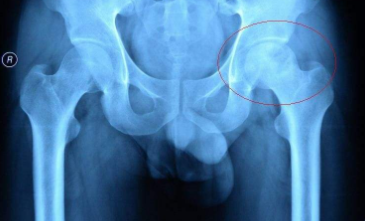

股骨头坏死的症状有哪些?河南股骨头坏死专科医院哪

河南股骨头坏死专科医院介绍股骨头坏死是较为常见的骨科疾病,多数患者有长期酗酒史、激素…[详情]

股骨头坏死怎么治疗?郑州痛风风湿病骨科医院

郑州痛风风湿病骨科医院介绍首先对股骨头坏死的病因做一个具体阐述。股骨头坏死最常见的是…[详情]